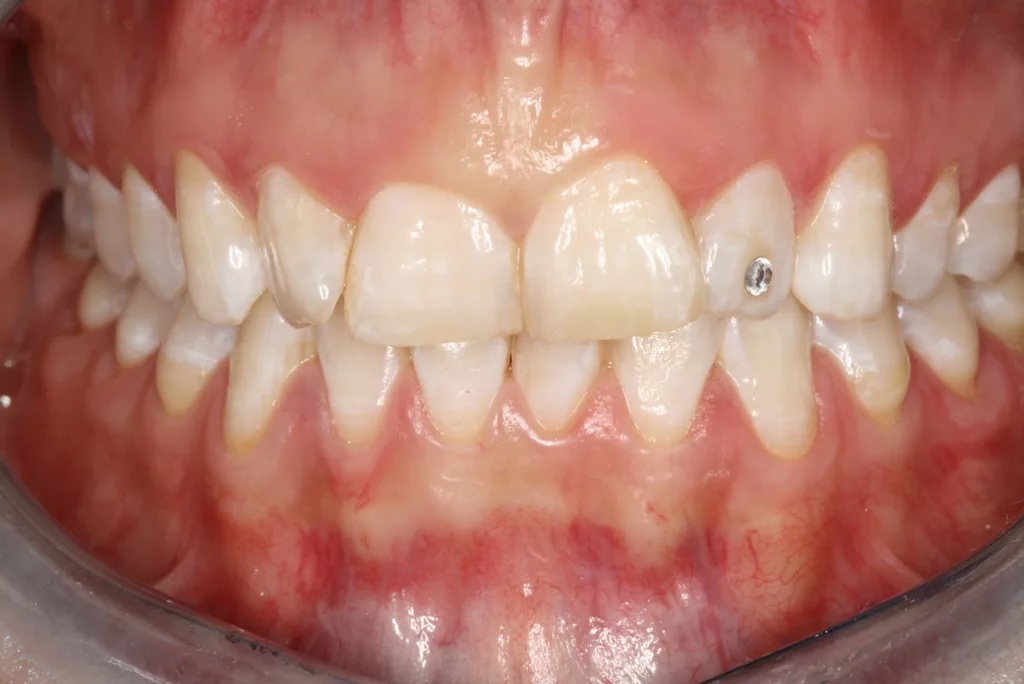

![Abb. 3a: Klinische Dokumentation einer 24-jährigen Patientin mit einer weit fortgeschrittenen lokalen parodontalen Destruktion, die mit großer Wahrscheinlichkeit durch ein Zungenpiercing hervorgerufen wurde [10]. Mit Ausnahme der Symptomatik im Unterkiefer-Frontzahnbereich wies die Patientin flache Sondierungstiefen und einzelne Regionen mit Gingivitis auf. Die Zähne reagierten positiv auf eine Sensibilitätsprobe mit Kältespray. Das Piercing war zum Zeitpunkt der Vorstellung in der Klinik bereits nicht mehr im Mund. Es wurde eine stufenweise systematische parodontale Therapie eingeleitet. Die verbliebenen und nahezu unveränderten erhöhten Son¬dierungstiefen wurden einem parodontal-chirurgischen Eingriff mit zusätzlichen, die Regenera¬tion fördernden Maßnahmen (Straumann Emdogain, Straumann, Basel, Schweiz) unterzogen. Es wurde die für diese Operationen empfohlene Schnittführung im Sinne eines Papillenerhaltungs¬lappens angewendet. Der nach der Degranulierung mit Hand- und Ultraschallinstrumenten sicht¬bare knöcherne Defekt wies eine ungünstige Morphologie für die Regeneration auf. Ein primärer Wundverschluss wurde dennoch erzielt. Diese Ansätze blieben letztendlich erfolglos und der Zahn 41 ging verloren (parodontologische Therapie gemeinsam mit Dr. L. Büttel, Basel, Schweiz).](https://dentalwelt.spitta.de/wp-content/uploads/2025/07/Abb-3a-1024x684.webp)

![Abb. 3b: Klinische Dokumentation einer 24-jährigen Patientin mit einer weit fortgeschrittenen lokalen parodontalen Destruktion, die mit großer Wahrscheinlichkeit durch ein Zungenpiercing hervorgerufen wurde [10]. Mit Ausnahme der Symptomatik im Unterkiefer-Frontzahnbereich wies die Patientin flache Sondierungstiefen und einzelne Regionen mit Gingivitis auf. Die Zähne reagierten positiv auf eine Sensibilitätsprobe mit Kältespray. Das Piercing war zum Zeitpunkt der Vorstellung in der Klinik bereits nicht mehr im Mund. Es wurde eine stufenweise systematische parodontale Therapie eingeleitet. Die verbliebenen und nahezu unveränderten erhöhten Son¬dierungstiefen wurden einem parodontal-chirurgischen Eingriff mit zusätzlichen, die Regenera¬tion fördernden Maßnahmen (Straumann Emdogain, Straumann, Basel, Schweiz) unterzogen. Es wurde die für diese Operationen empfohlene Schnittführung im Sinne eines Papillenerhaltungs¬lappens angewendet. Der nach der Degranulierung mit Hand- und Ultraschallinstrumenten sicht¬bare knöcherne Defekt wies eine ungünstige Morphologie für die Regeneration auf. Ein primärer Wundverschluss wurde dennoch erzielt. Diese Ansätze blieben letztendlich erfolglos und der Zahn 41 ging verloren (parodontologische Therapie gemeinsam mit Dr. L. Büttel, Basel, Schweiz).](https://dentalwelt.spitta.de/wp-content/uploads/2025/07/Abb-3b-1024x684.webp)

![Abb. 3c: Klinische Dokumentation einer 24-jährigen Patientin mit einer weit fortgeschrittenen lokalen parodontalen Destruktion, die mit großer Wahrscheinlichkeit durch ein Zungenpiercing hervorgerufen wurde [10]. Mit Ausnahme der Symptomatik im Unterkiefer-Frontzahnbereich wies die Patientin flache Sondierungstiefen und einzelne Regionen mit Gingivitis auf. Die Zähne reagierten positiv auf eine Sensibilitätsprobe mit Kältespray. Das Piercing war zum Zeitpunkt der Vorstellung in der Klinik bereits nicht mehr im Mund. Es wurde eine stufenweise systematische parodontale Therapie eingeleitet. Die verbliebenen und nahezu unveränderten erhöhten Son¬dierungstiefen wurden einem parodontal-chirurgischen Eingriff mit zusätzlichen, die Regenera¬tion fördernden Maßnahmen (Straumann Emdogain, Straumann, Basel, Schweiz) unterzogen. Es wurde die für diese Operationen empfohlene Schnittführung im Sinne eines Papillenerhaltungs¬lappens angewendet. Der nach der Degranulierung mit Hand- und Ultraschallinstrumenten sicht¬bare knöcherne Defekt wies eine ungünstige Morphologie für die Regeneration auf. Ein primärer Wundverschluss wurde dennoch erzielt. Diese Ansätze blieben letztendlich erfolglos und der Zahn 41 ging verloren (parodontologische Therapie gemeinsam mit Dr. L. Büttel, Basel, Schweiz).](https://dentalwelt.spitta.de/wp-content/uploads/2025/07/Abb-3c-1024x722.webp)

![Abb. 3d: Klinische Dokumentation einer 24-jährigen Patientin mit einer weit fortgeschrittenen lokalen parodontalen Destruktion, die mit großer Wahrscheinlichkeit durch ein Zungenpiercing hervorgerufen wurde [10]. Mit Ausnahme der Symptomatik im Unterkiefer-Frontzahnbereich wies die Patientin flache Sondierungstiefen und einzelne Regionen mit Gingivitis auf. Die Zähne reagierten positiv auf eine Sensibilitätsprobe mit Kältespray. Das Piercing war zum Zeitpunkt der Vorstellung in der Klinik bereits nicht mehr im Mund. Es wurde eine stufenweise systematische parodontale Therapie eingeleitet. Die verbliebenen und nahezu unveränderten erhöhten Son¬dierungstiefen wurden einem parodontal-chirurgischen Eingriff mit zusätzlichen, die Regenera¬tion fördernden Maßnahmen (Straumann Emdogain, Straumann, Basel, Schweiz) unterzogen. Es wurde die für diese Operationen empfohlene Schnittführung im Sinne eines Papillenerhaltungs¬lappens angewendet. Der nach der Degranulierung mit Hand- und Ultraschallinstrumenten sicht¬bare knöcherne Defekt wies eine ungünstige Morphologie für die Regeneration auf. Ein primärer Wundverschluss wurde dennoch erzielt. Diese Ansätze blieben letztendlich erfolglos und der Zahn 41 ging verloren (parodontologische Therapie gemeinsam mit Dr. L. Büttel, Basel, Schweiz).](https://dentalwelt.spitta.de/wp-content/uploads/2025/07/Abb-3d-1024x665.webp)

Wir sind vor mittlerweile 17 Jahren erstmals mit der Frage etwaiger Auswirkungen oraler Piercings auf den Zahnhalteapparat konfrontiert worden [10]. Eine damals 24-jährige Patientin stellte sich mit einem ungewöhnlichen Befund vor (Abb. 3a bis d). Bei sonst parodontal unauffälligen Verhältnissen mit Sondierungstiefen zwischen 2 und 3 mm, reichten die Sondierungstiefen an den Schneidezähnen im Unterkiefer bis 12 mm. Zahn 41 schmerzte und wies eine erhöhte Lockerung von Grad 2 auf. Bukkal war zudem eine Fistel mit Pusentleerung zu detektieren. Die Patientin war allgemeinmedizinisch gesund, rauchte nicht und hatte auch keinen Diabetes mellitus. Eine familiäre Prädisposition für parodontale Erkrankungen ließ sich anamnestisch nicht konstruieren. Die Mundhygiene war zwar nicht perfekt, stand aber auch in keinem Verhältnis zu ihrem dramatischen lokalen parodontalen Befund. Im Rahmen der anamnestischen Befragung, fokussiert auf ungewöhnliche Habits, berichtete die Patientin, bis vor kurzem ein Zungenpiercing getragen zu haben, dieses aber vor ca. sechs Monaten entfernt zu haben. Die Piercing-Tragedauer betrug etwa drei Jahre.

In der Gesamtschau der zusammengetragenen Daten und unter Berücksichtigung der in medizinischen Datenbanken aufgefundenen einzelnen Fallbeschreibungen erschien uns die wahrscheinlichste Ursache für den vorliegenden Befund tatsächlich das Zungenpiercing zu sein [11]. Die parodontale nicht-chirurgische, wie auch die chirurgisch-regenerative Therapie waren nicht erfolgreich und die Patientin verlor den stark kompromittierten Unterkiefer-Frontzahn. Seit dieser Zeit beschäftigen wir uns intensiver mit diesem Thema. So begannen wir mit der Sammlung und Erfassung der klinischen Parameter bei Patienten/-innen, die ein orales Piercing tragen oder einst trugen. Die Ergebnisse wurden zunächst im Rahmen einer Masterarbeit ausgewertet, als Posterbeitrag bei der Europerio 9 in Amsterdam veröffentlicht und später dann als Manuskript publiziert [10,12].